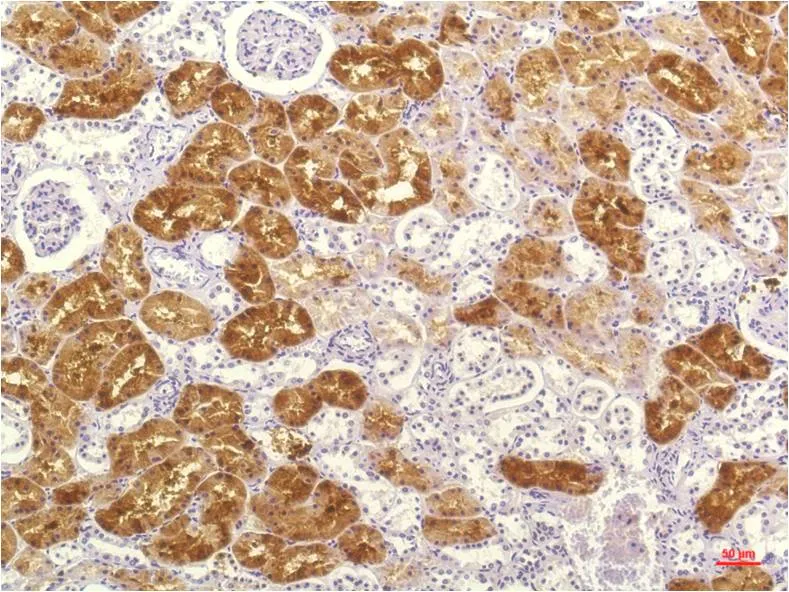

JAK2 (6B4) Mouse Monoclonal Antibody

Cat: AMM00767

Application:IHC-P

Reactivity:Human,Rat,Mouse

Conjugate:Unconjugated

Gene Name:JAK2